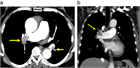

病態

1. 急性肺塞栓症とは、静脈系にできた塞栓子(大部分が血栓)が肺動脈を閉塞させ、その結果、肺動脈の血流が障害されて呼吸や循環に異常を来した状態をいう。